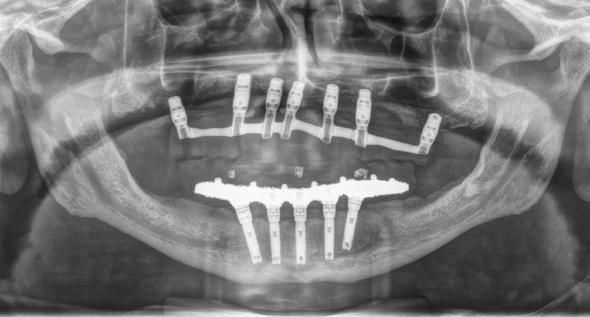

Figura 2 y 3. Figuras intraorales del paciente de 67 años que acude a la consulta para rehabilitación sobre implantes superior, portador de una prótesis completa removible con una atrofia ósea evidente al ser la prótesis retirada. Figura 4. La radiografía inicial muestra una atrofia marcada en sentido vertical, que debe ser constatada posteriormente mediante un TAC así como para la planificación de la colocación de los implantes. Figura 5 y 6. Encerado diagnóstico para comenzar la planificación de la colocación de los implantes superiores guiados por la posición ideal que deben tener los dientes en la prótesis. De este encerado se realiza una guía radiológica que nos permita trasladar estas posiciones al TAC de planificación.

Fueron reclutados 6 pacientes en los que se colocaron 30 implantes para realizar rehabilitaciones completas. La edad media de los pacientes incluidos en el estudio fue de 66.75 años (+/- 5,16) y un 86.7% fueron mujeres. El 63.3% de los implantes se insertaron en el maxilar superior y el 36.7% restante en la mandíbula, formando parte de 4 rehabilitaciones

completas superiores y 3 inferiores. Todos los implantes presentaron una longitud de 5.5 m m, con diámetros comprendidos entre los 2.5 y los 5.5 mm. Las posiciones de los implantes corresponden a distribuciones biomecánicas para la realización de prótesis completas tanto en el maxilar como mandíbula (incisivos, premolares y molares). Los diámetros y longitudes de los implantes incluidos en el estudio en función de

181. Septiembre 2023 51 Rehabilitaciones completas implantosoportadas

su posición se muestran en la Figura 1.

Figura 7­9. Cortes de planificación del cone beam donde observamos la extrema atrofia vertical y la posición en la que deberían situarse los dientes con una gran discrepancia entre esta posición y la base ósea. Vemos también como se planifican implantes extracortos de 5.5 mm de longitud en todas las localizaciones. Figura 10. Radiografía panorámica tras la colocación de los implantes.